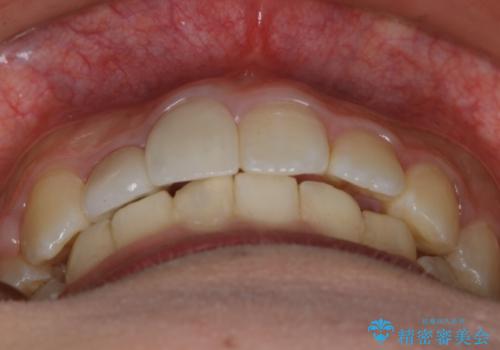

また、右下の歯が生まれつき少なく、隙間が空いている状態でした。

矯正治療でご自身の歯を移動して閉じることにしました。

また、咬んだときに下の前歯が隠れる過蓋咬合でしたが、矯正治療で改善しました。